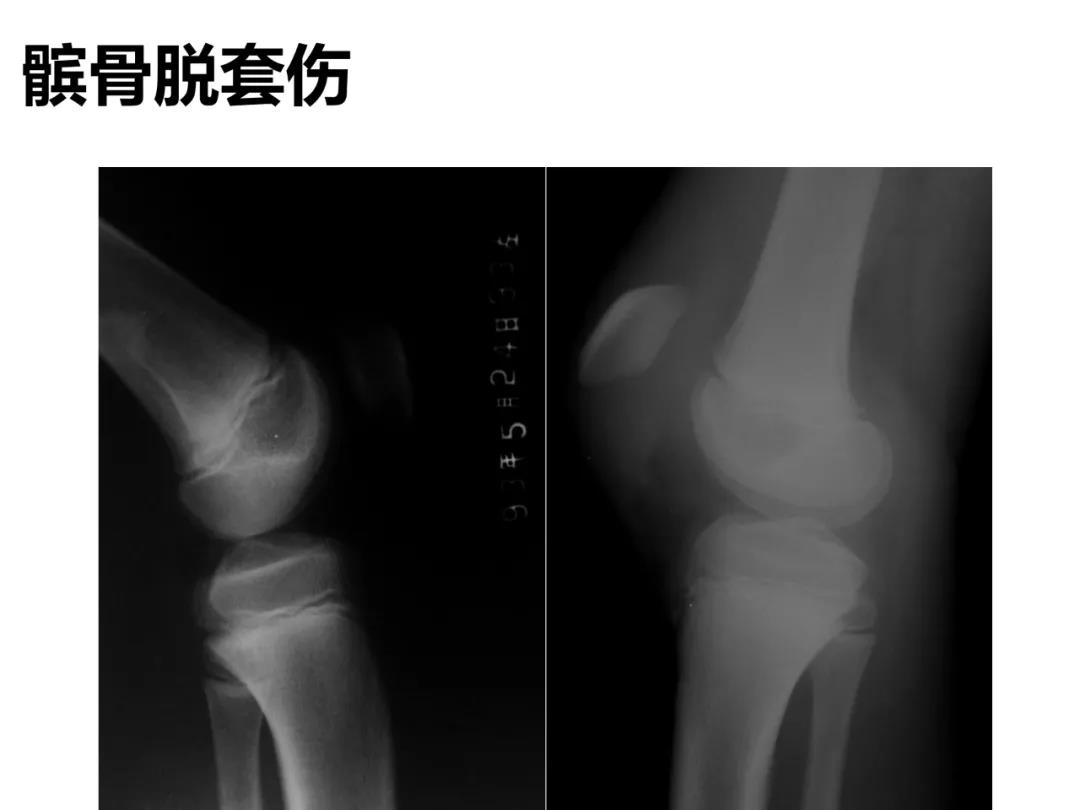

小儿骨科X线片汇总,临床读片宝典!